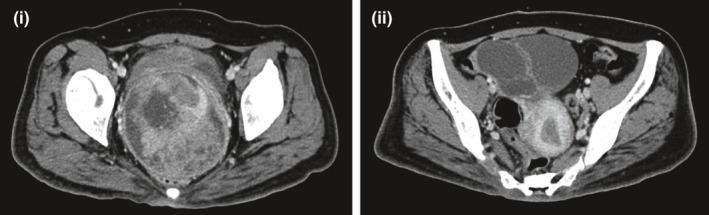

癌症患者中共济失调毛细血管扩张症的识别:一个有趣病例的新见解及文献综述

Identifying ataxia-telangiectasia in cancer patients: Novel insights from an interesting case and review of literature.

Timely genetic testing leading to early diagnosis of A-T is crucial due to its plethora of implications on clinical management, particularly in those who develop malignancies. Thus, clinicians have to be astute in identifying diagnostic clues of A-T.

由于共济失调毛细血管扩张症(A-T)对临床管理有诸多影响,尤其是对那些发生恶性肿瘤的患者,及时进行基因检测以实现早期诊断至关重要。因此,临床医生必须敏锐地识别A-T的诊断线索。